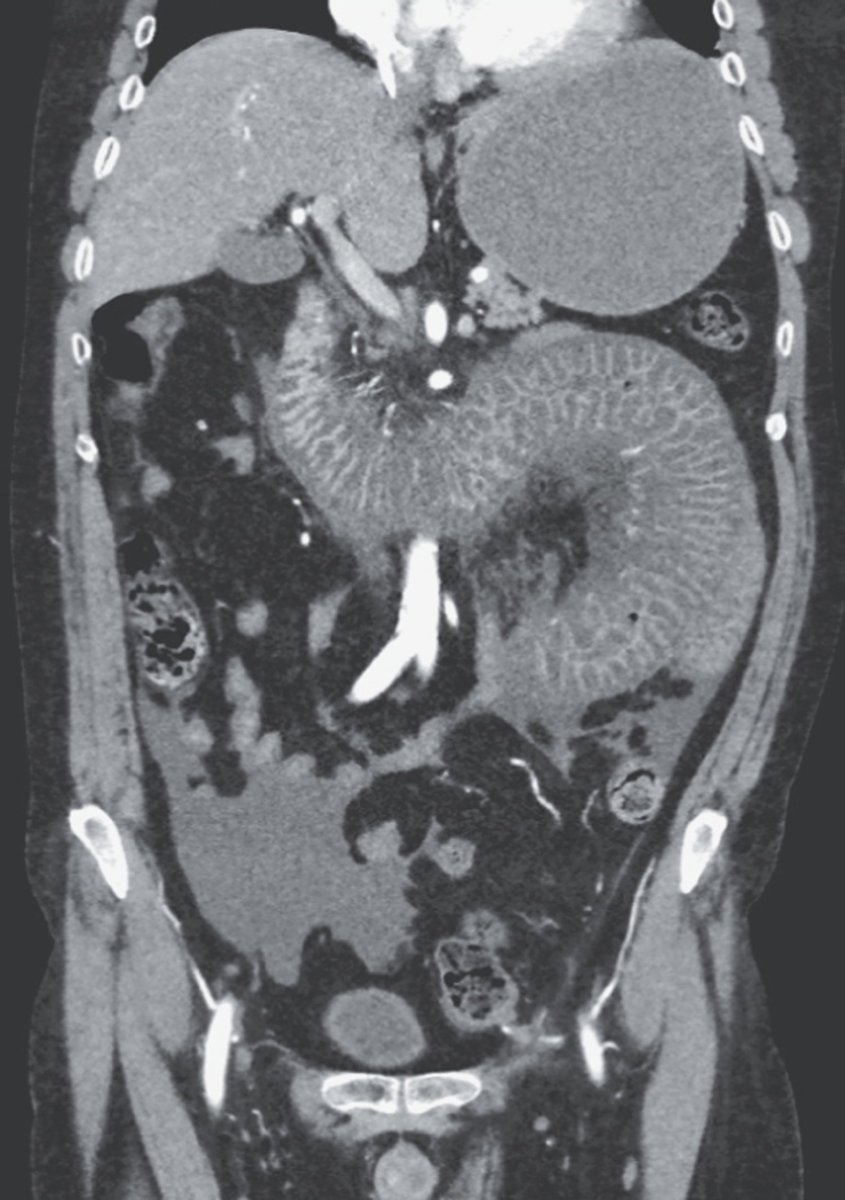

Which one is likely to be positive in a man with acute renal failure and these findings? *IgA anti-tissue transglutaminase *IgG antibodies against Lyme disease *Helicobacter pylori stool antigen *Antimitochondrial antibodies *Antineutrophil cytoplasmic autoantibody

Antineutrophil cytoplasmic autoantibody. Granulomatosis with polyangiitis (GPA) is one of the ANCA-associated vasculitides. Patients with GPA typically present with constitutional prodromal symptoms such as weight loss, malaise, and fever.

Gastrointestinal Complication of Granulomatosis with Polyangiitis - CTA was highly suggestive of bowel ischemia with wall thickening of the distal duodenum and jejunal loops (white arrow) with adjacent fat stranding and mesenteric edema (orange arrow) and free fluid in the

Typical involvement includes the ear, nose, and throat, lung, cutaneous organs, and the kidneys, with glomerulonephritis. Neurological manifestations such as neuropathy, cardiac involvement, and gastrointestinal issues can also occur, as is the case here with bowel ischemia,